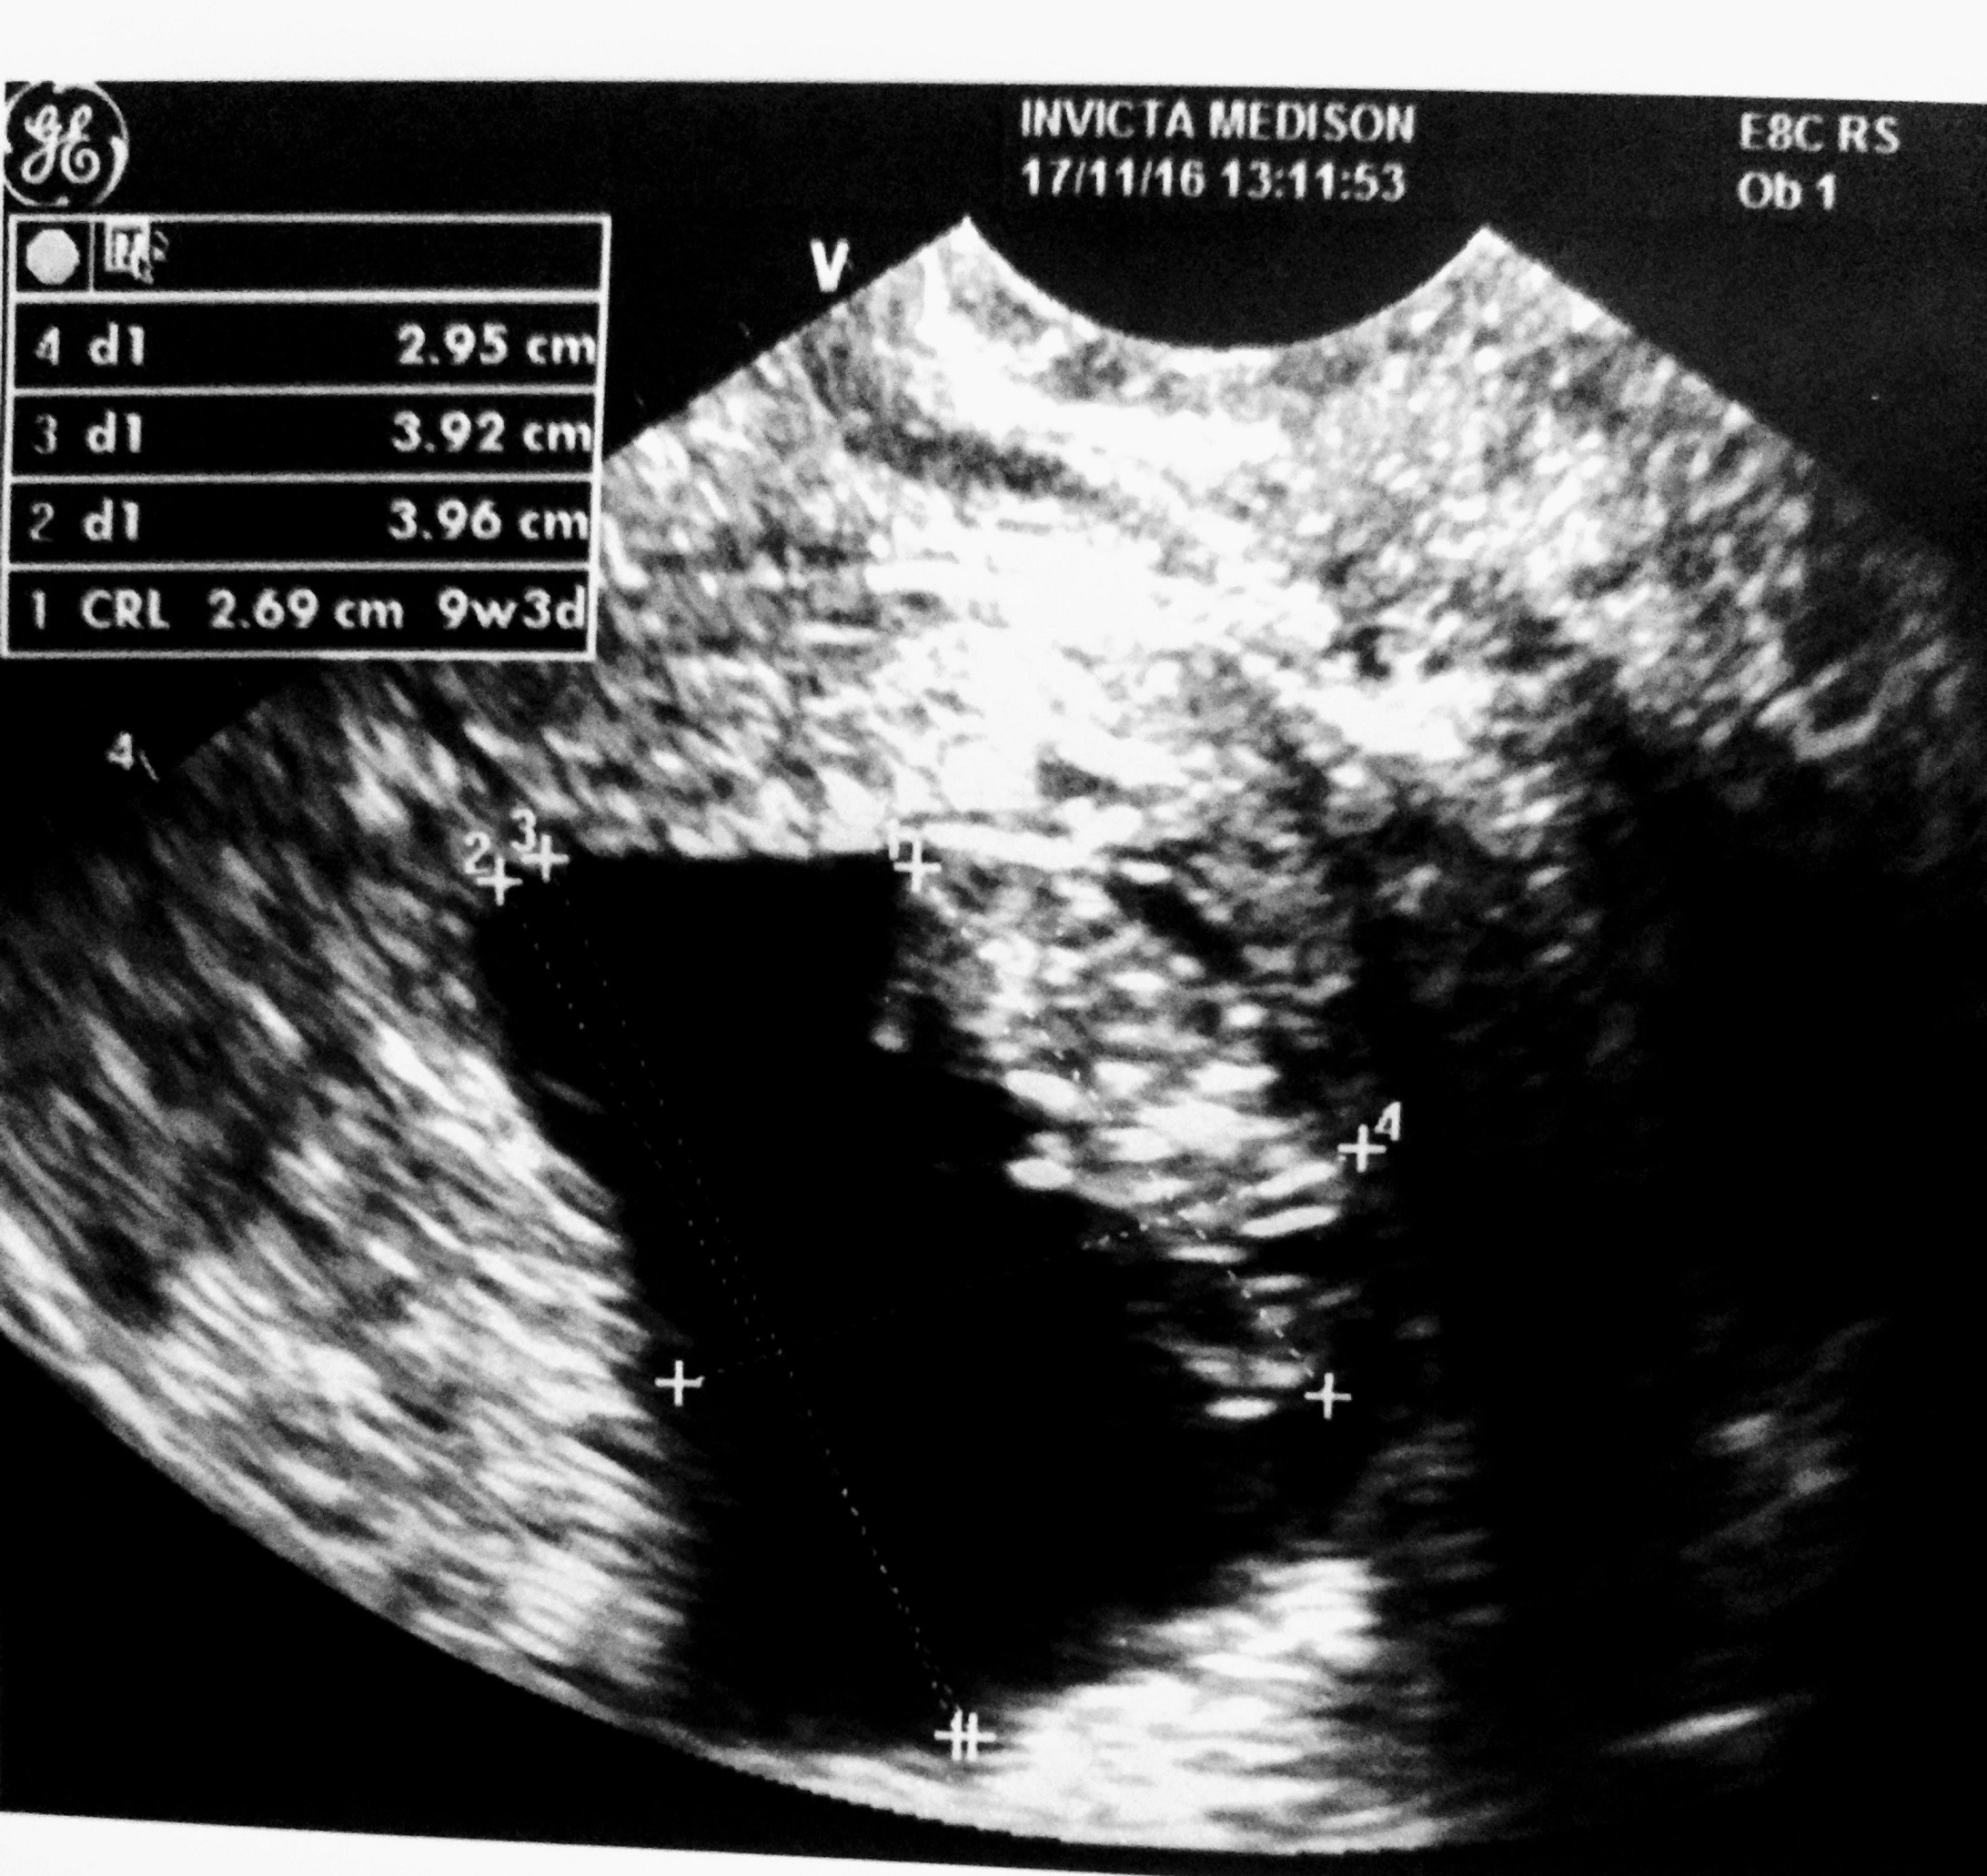

i najważniejsze na koniec, zrobiła mi USG!!! Maleństwo całe i zdrowe, z bijącym serduszkiem 162 uderzenia na minutę, cudownie do nas machało rączkami. Wzruszyłam się niesamowicie, aż miałam łzy szczęścia w oczach, kamień spadł mi z serca. Okazało się, że ma już 2,7 cm a nie tak jak przedwczoraj na IP mi na tym zażółkłym sprztem wyliczyli, że 1,9 cm... no raczej aż tyle nie urosło w niecałe 2 dni.

I jestem przeszczęśliwa, bo to zgadza się z badaniem sprzed 3 tygodni, gdzie ciąża była młodsza o 5 dni, to teraz już tylko o 4 dni jest młodsza. Szczęśliwa mamusia = szczęśliwe dzidzi